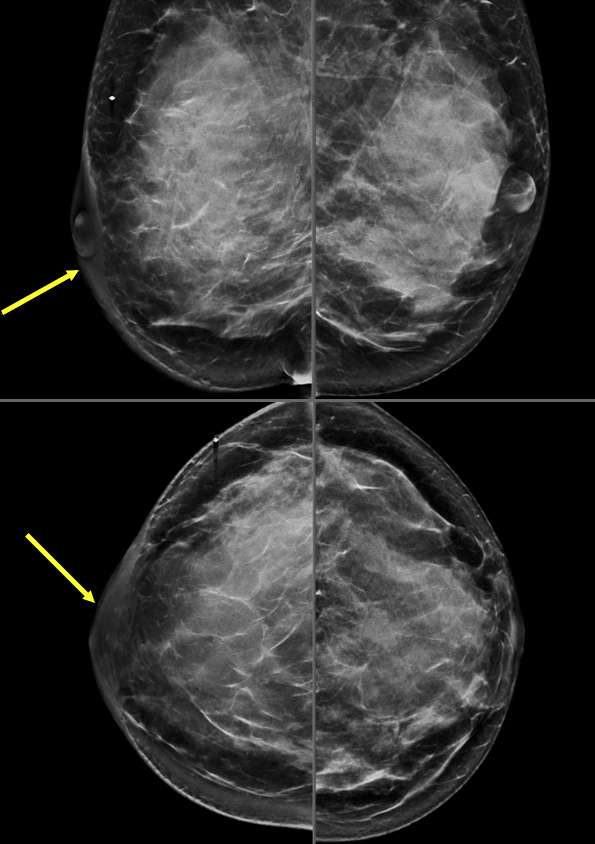

- Mammography: Skin retraction may be noted as an irregular, pulled appearance of the skin. An underlying mass may or may not be mammographically visible.

- Mammography: Demonstrates a nipple that lays flat or points inwards rather than protruding outward. Sometimes, a mass can be seen in the subareolar area causing the nipple inversion.